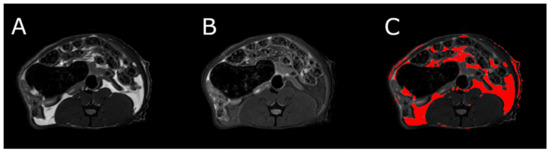

MRI measurements showed a significant reduction in the adipose tissue volume of ABA rats compared with controls (Figure 5). The mean visceral body fat reduction in the ABA rats reached 58.9% on day 6 of the experiment (Figure 6).

Figure 6.

MRI scan of female ABA rat, the cross section of the abdomen at L4 level. (A) RARE image without fat suppression; (B) fsupRARE image with fat suppression; (C) segmentation result—adipose tissue marked in red.

MRI was used to determine the volume of visceral and subcutaneous adipose tissue at the level of the L4 vertebra in healthy and ABA rats. MRI experiments were performed on a 9.4T Bruker Biospec scanner, using a Bruker T9361 transmit/receive birdcage coil with a diameter of 72 mm. Animals were euthanized with pentobarbital prior to imaging (Morbital, Biowet, Pulawy; 1–2 mL/kg b.wt.) after ketamine/xylazine premedication to obtain high-quality images devoid of any artifacts. Imaging was performed using the fast spin-echo rapid acquisition with a relaxation enhancement sequence (RARE). Pulse sequence parameters were echo time = 6.3 ms, repetition time = 2000 ms, RARE factor = 8, acquisition matrix = 256 × 256, field of view = 60 × 60 mm, and number of slices = 23. The entire abdomen from L1 to L6 was covered with 1 mm thick axial slices. Imaging was done twice, first without fat suppression (RARE) and repeated with the fat suppression module (fsupRARE) turned on. In the images obtained with the spin-echo sequence, fat appears as a bright area. This area becomes correspondingly darker when fat suppression is used. This relationship was used to find image pixels containing fat. Adipose tissue segmentation was performed using a custom-developed MATLAB script (The Mathworks, Inc.). The slice passing through the L4 vertebra in the reference anatomical image was selected for further analysis. First, the pixel values of both images were normalized to 1. The difference between the normalized RARE and fsupRARE images was then calculated—the fat containing pixels were those for which the difference image pixel value was greater than 0.2. Finally, adipose tissue volume was calculated as the product of the number of pixels containing fat and the volume of a single pixel.